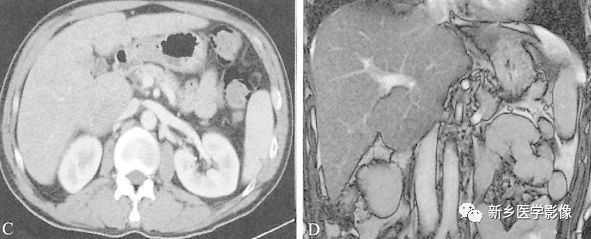

3先天性肝叶缺如:

肝右叶缺如居多,多合并胆囊缺如,左叶代偿性增大,密度均匀,常合并肝内胆管轻度扩张;增强扫描门静脉主干及左支增粗,右支不显影。鉴别诊断:术后改变;肝硬化;创伤。